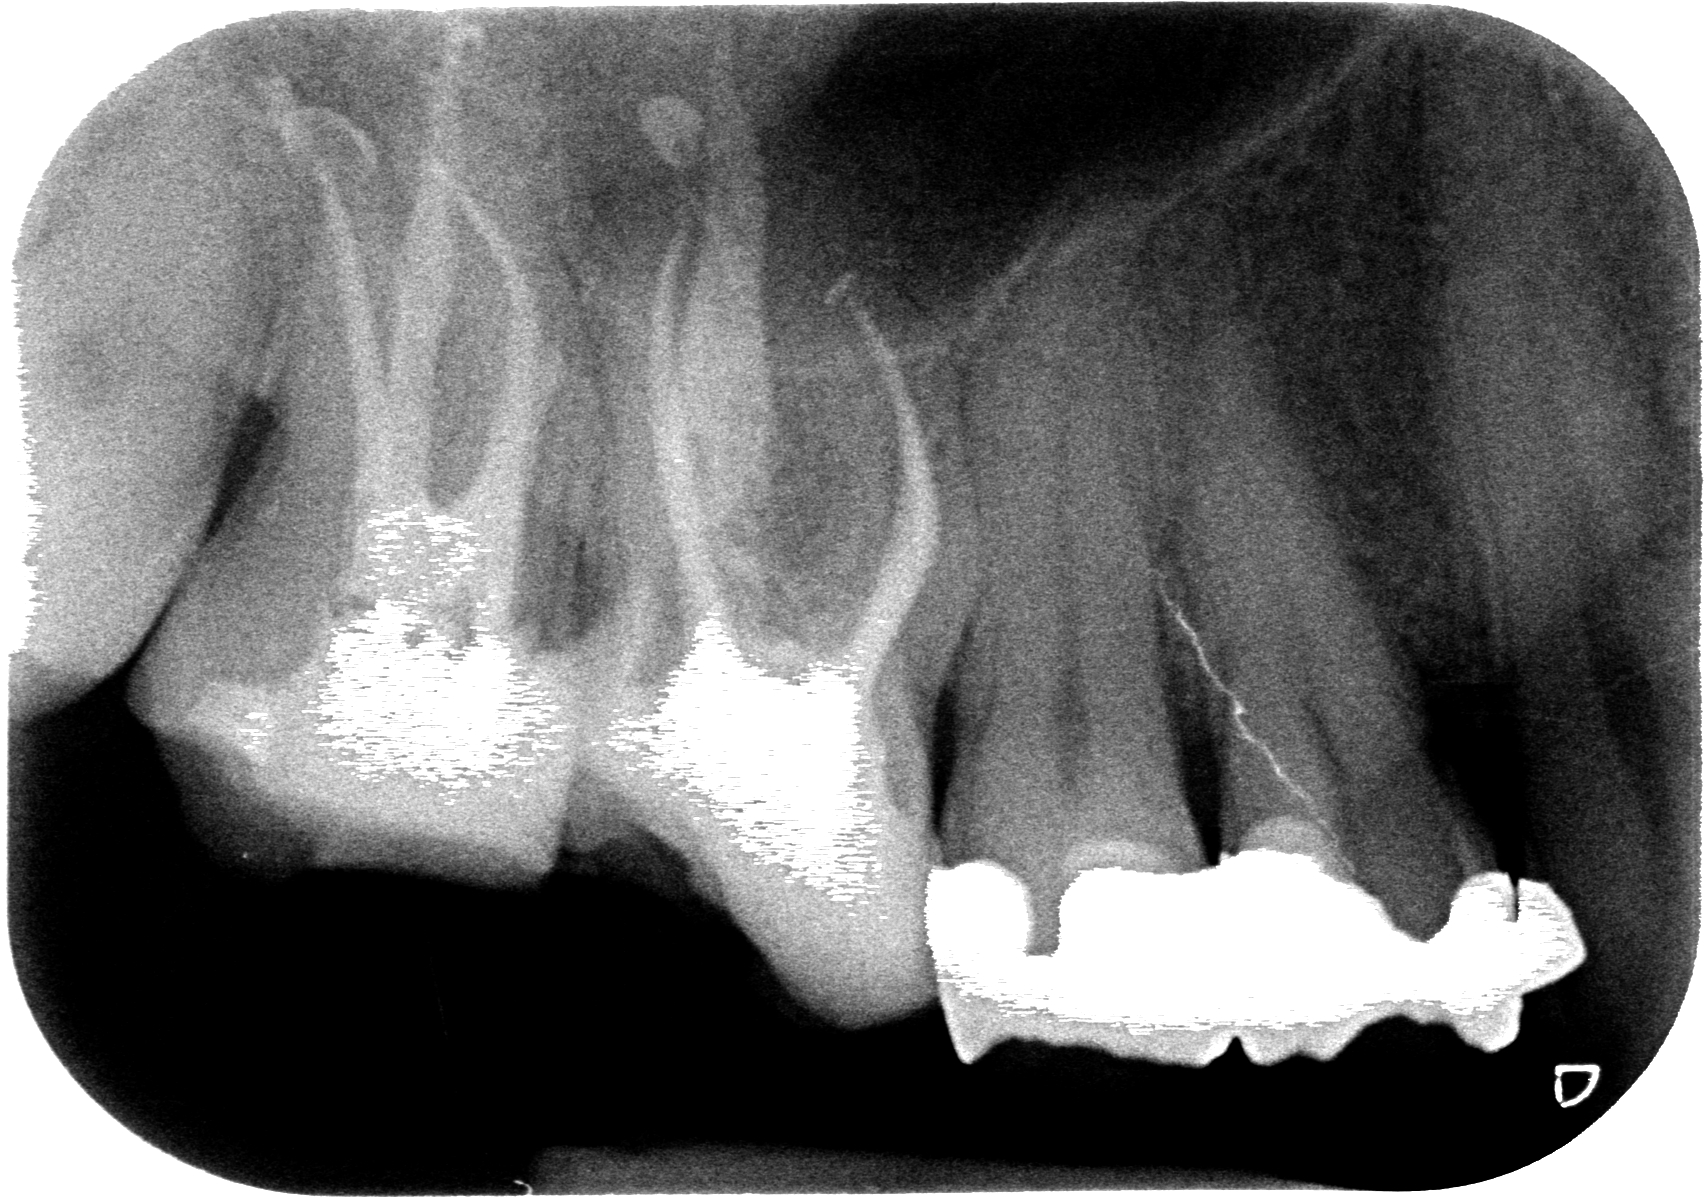

Strumento, irrigo e chiudo con Thermafil.

Voilà.

Per prendermi la meritata soddisfazione attendo col paziente che Anna, la mia assistente, vada a sviluppare la rx finale per vederla assieme.

E il risultato parla da solo e lo capisce anche il paziente, che ha capito di essere il buone mani. Ha trovato un professionista di cui sa di potersi fidare e percepisce anche il valore economico della terapia come giusto, viste le due ore impiegate e le attrezzature, le competenze e le abilità dimostrate.